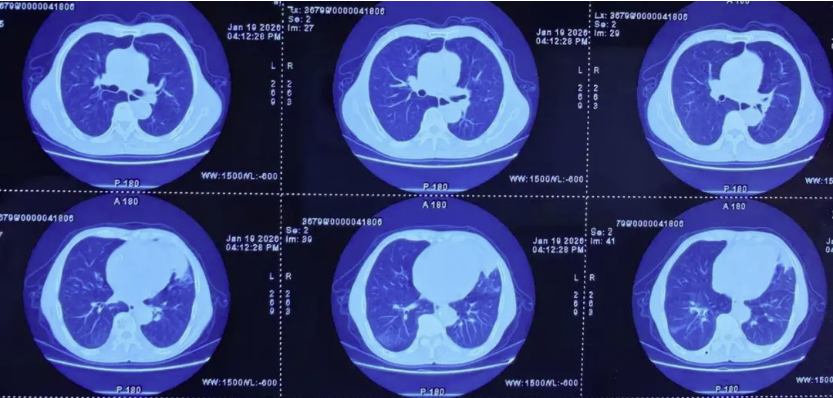

治疗:患者同意参加由中日友好医院牵头,上海市肺科医院为参与单位的临床研究《两性霉素B脂质体 (AmBisome®)联合艾沙康唑与AmBisome®单药治疗肺毛霉菌病的疗效和安全性比较的多中心、前瞻性、开放、随机对照研究》,通过随机化入组了两性霉素B脂质体单药治疗组。2026年2月13日起予两性霉素B脂质体5mg/kg/d静滴治疗,2月16日复查肾功能示血肌酐111.6umol/L升高,考虑肾功能损伤,2月17日起两性霉素B脂质体减量至3mg/kg/d静滴治疗,同时予水化、保肾等治疗。2月19日复查肾功能血肌酐98.7umol/L,较前有下降好转,继续两性霉素B脂质体3mg/kg/d静滴治疗,监测血常规、肝肾功能电解质。2月23日复查胸片示左肺实变影较前有所吸收好转(图片3)。两性霉素B脂质体静滴疗程满28天,2026年3月11日复查胸部CT示左肺实变影基本完全吸收好转(图片4)。2026年3月12日予出院续贯口服艾沙康唑治疗。在药物治疗的同时,营养支持也很重要,患者入院时血生化示白蛋白32.1g/L,前白蛋白120.3mg/L,遵医嘱每日食用3-4个鸡蛋补充蛋白质,出院时白蛋白升至43.4g/L,前白蛋白318.5mg/L(图片5)。

图片4:两性霉素B脂质体静滴治疗28天胸部CT对比左肺实变影基本完全吸收好转。